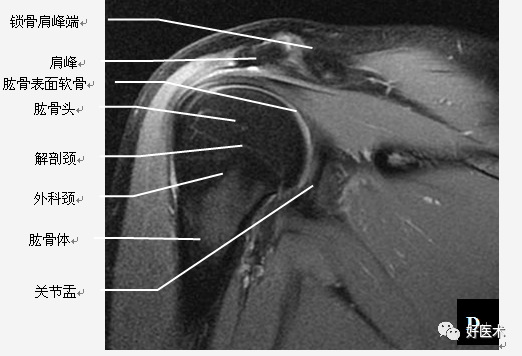

肩关节骨骼构成

三块骨:肩胛骨、锁骨、肱骨

两个关节:

肩锁关节

盂肱关节

肩关节固有肌群

(2)肩袖

肩袖是由冈上肌、冈下肌、小圆肌和肩胛下肌的肌腱构成。前三个肌腱由上向下均止于肱骨大结节,而肩胛下肌腱止于肱骨小结节。